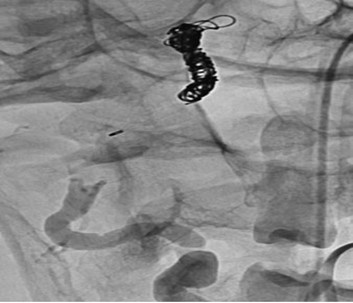

Given the posterior predominant SAH on CT imaging, we believed that this dissecting aneurysm was the source of the patient’s hemorrhages. The rest of the intracranial circulation was normal with no evidence of other aneurysm or arteriovenous malformation. She underwent endovascular embolization of the right vertebral artery dissecting aneurysm which required vessel sacrifice with coils and a vascular microplug (Figure 6).

Figure 6. Cerebral angiogram showing successful embolization with coils and MVP of the right vertebral artery dissecting aneurysm requiring vessel sacrifice.

Follow-up angiography demonstrated good occlusion of the dissecting aneurysm and right vertebral artery with no flow in this artery, and continued filling of the posterior circulation through the contralateral vertebral artery. The procedure was successful, and her care continued in the neurocritical care unit. She improved clinically, and was subsequently weaned from mechanical ventilation and successfully extubated in the 24 hours after the procedure, then placed on oxygen with a nasal cannula at 4 L/min. Her ECG continued to show T wave inversion and QT/QTc prolongation while she was not taking escitalopram. Cardiac evaluation with echocardiography demonstrated a mildly dilated left ventricle with normal wall thickness; normal ventricular mass; and preserved motion of the basal anterior, anterolateral, inferior, and inferoseptal segments of the left ventricle. The remaining segments were hypokinetic, and the apex appeared severely hypokinetic, with moderately reduced systolic function and an estimated ejection fraction of 30–35% with grade I diastolic dysfunction. These findings suggested stress-induced cardiomyopathy (Takotsubo cardiomyopathy) related to SAH.